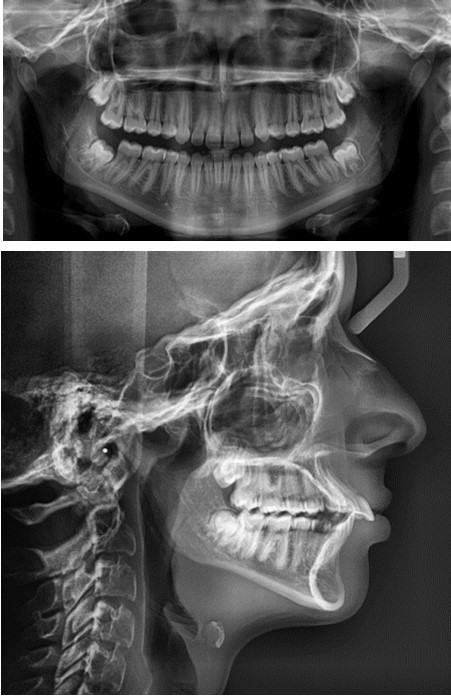

In order to emphasize one of the major indications of skeletal anchorage with mini implants, a clinical case was selected. A young teenage patient (Figure 1, Figure 2, Figure 3, Figure 4), with a severe overjet, flared upper incisors with spacingand a convex profile was reffered to our dental office. Treatment objectives were established from the beggining: retrusion of the upper anterior teeth, overjet and overbite correction, space closure and obtaining a better occlusion. Anchorage needs were evaluated. Absolute anchorage was needed in order to obtain upper dental retrusion without mesial movement of the posterior teeth. Two mini implants were placed bilaterally, in a labial position, between the second premolars and upper first molars. Both mini plates and mini implants provide a predictable result in this case but since mini implants are more easy to place and provide a higher degree of comfort, this option seemed more suitable. In this way, the need for other anchorage devices, such as a palatal arch or headgear was eliminated. The upper incisors and canines can be now distalized and intruded, after the upper premolar extraction.

Figure 1.The OPG and ceph radiograph of our patient